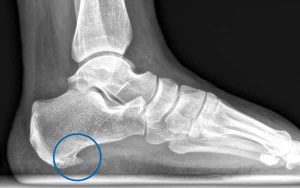

La fascitis plantar es una de las causas más frecuentes de dolor en el talón. Se trata de una inflamación de la fascia plantar, un tejido fibroso que conecta el talón con la base de los dedos y que resulta fundamental para mantener el arco del pie y absorber impactos al caminar o correr.